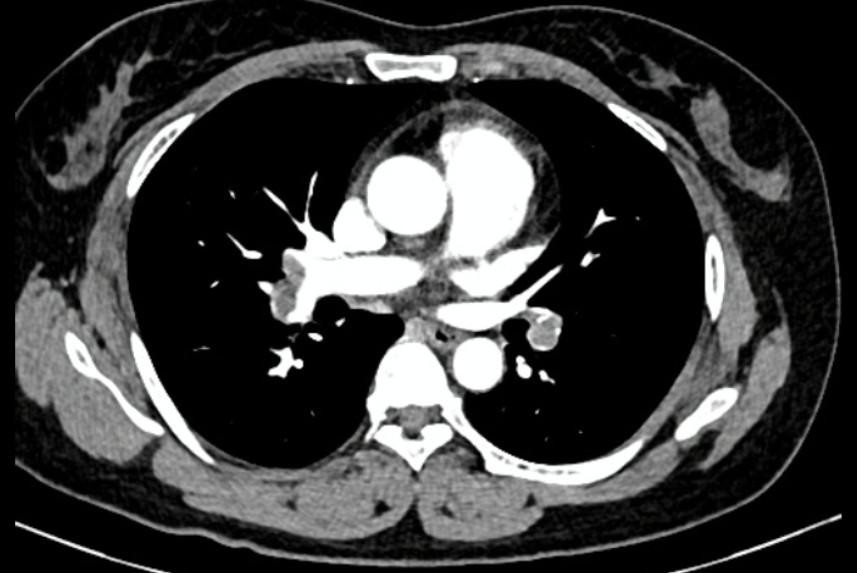

Qua chẩn đoán bằng hình ảnh, các bác sĩ phát hiện động mạch phổi hai bên của người bệnh bị huyết khối lớn che lấp hoàn toàn và chẩn đoán bệnh nhân bị thuyên tắc phổi nên chuyển đến khoa Hồi sức Tim mạch. Tại đây, bệnh nhân đã rơi vào tình trạng khó thở, suy hô hấp, giảm ô xy, nhịp tim nhanh và huyết áp thấp. Các bác sĩ chỉ định dùng tiêu sợi huyết truyền qua đường tĩnh mạch cho người bệnh.

| Hỉnh ảnh kiểm tra cho thấy người bệnh bị thuyên tắc động mạch phổi cả 2 bên |